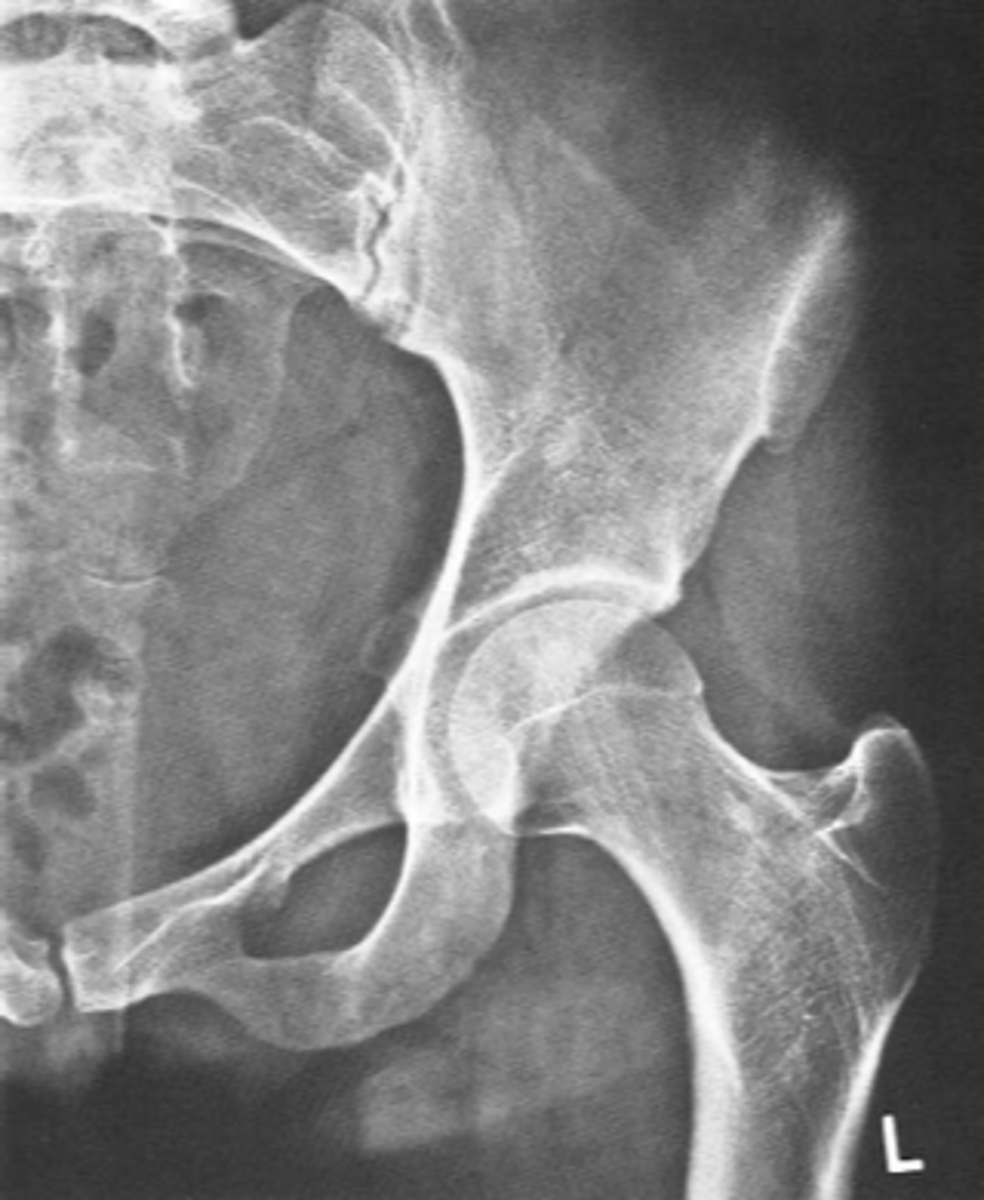

Shenton's line

ID measurement

<p>ID measurement</p>

- AP hip

- AP pelvis

What views are used to see Shenton's line?

- Smooth arc along femoral neck

- Obturator foramen

Shenton's line landmarks

Continuous and smooth

Shenton's line normal measurements

<p>Shenton's line normal measurements</p>

- Hip dislocation

- Femoral neck fracture

- Slipped epiphysis

Clinical significance of Shenton's line

<p>Clinical significance of Shenton's line</p>

Femoral angle

What views are used to measure the femoral angle?

- Mid-axis of femoral shaft

- Mid-axis of femoral neck

- Intervening angle

Femoral angle landmarks

120-130˚

Normal femoral angle measurement

<p>Normal femoral angle measurement</p>

Coxa vara

Femoral angle <120˚

<p>Femoral angle &lt;120˚</p>

Coxa valga

Femoral angle >130˚

<p>Femoral angle &gt;130˚</p>

Skinner's line

What views are used to see Skinner's line?

- Right angle tangent to tip of greater trochanter

Skinner's line landmarks

<p>Skinner's line landmarks</p>

Fovea capitis should lie above or at level of trochanteric line

Skinner's line normal measurement

<p>Skinner's line normal measurement</p>

Fracture or other causes of coxa vara

Clinical significance of Skinner's line

<p>Clinical significance of Skinner's line</p>

Klein's line

What views are used to see Klein's line?

Line along femoral neck

Klein's line landmarks

<p>Klein's line landmarks</p>

Line should intersect portion of femoral head

Klein's line normal measurement

<p>Klein's line normal measurement</p>

Slipped capital femoral epiphysis

Clinical significance of Klein's line

<p>Clinical significance of Klein's line</p>